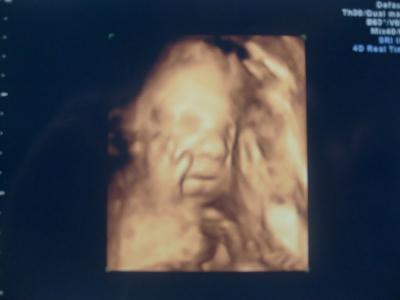

Boah die Zeit vergeht wie im Fluge, wahnsinn. Hier mal die Fakten: Alles super entwickelt und versorgt, hat auch seine Männlichkeit nochmal in aller Deutlichkeit in die "Kamera" gehalten. Ich hab auch mal was neues, ich hab keine Hinterwandplazenta, wie er beim ersten US meinte, auch keine Vorderwandplazenta, wie beim 2. mal, dieses mal ist es eine Seitenwandplazenta *kicher* Werte zum Vergleich von 29+5 BPD: 8,1 KU: 29 ATD: 7,7 AU: 24,9 FL: 5,5 Gewicht lt. Arzt 1414g Doppler O.B. Kind super versorgt, viel Fruchtwasser, Grannum Grad 0 Juhuu! Wir haben sogar einfach mal so ein 3D Bildchen von ihm bekommen :) Naja, erkennt man nicht viel drauf, ist etwas unscharf mal wieder mit der Kamera abfotografiert und er hat die Hand am Gesicht.

Das ist aber ein schönes Foto. Mein FA macht einen Ultraschall bei jeder 2. VU. Egal ob wöchentlich oder nicht. Ich finds gut